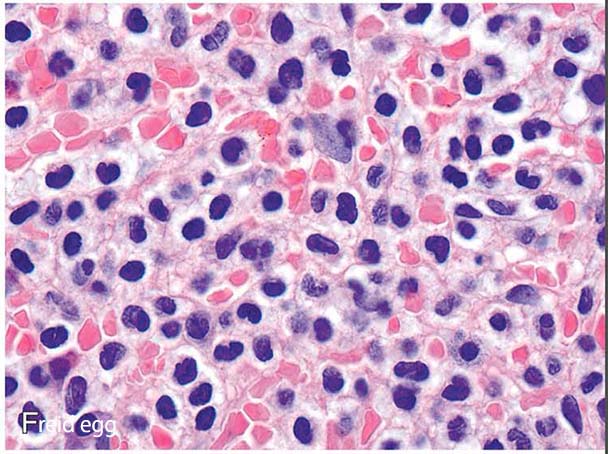

fried egg.jpg

骨髄(BM)は,HCLによる骨髄線維化とHairy細胞の細胞境界の連鎖のため,しばしば吸引が困難か不可能である(dry tap)。そのため,診断は末梢血とtrephine biopsyの分析に大きく依存する.

骨髄を侵すヘアリー細胞白血病

滲出した赤血球がしばしばみられ,脾臓で最もよくみられる有毛細胞で裏打ちされた空間に赤血球が集まった "血餅 "がみられることもある。有糸分裂像はまれで,腫瘍細胞の壊死やアポトーシスはみられない

脾臓: 脾臓は,腫瘍細胞の赤脾髄びまん性浸潤と拡大により著明な腫大を示し,白脾髄の萎縮を伴う.*56腫瘍浸潤は,細胞質が明瞭な中型細胞の単調な集団で構成され,"目玉焼き "のような外観を呈する(Fig3).拡張した洞は赤血球で満たされ,"血の池"("仮性洞 "とも呼ばれる)を形成することがある。